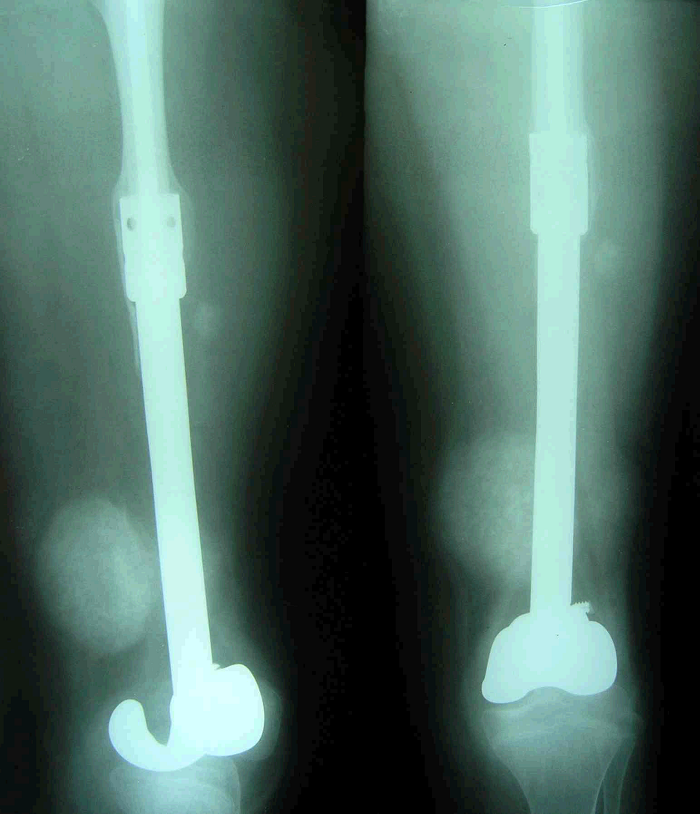

3、病例3:女 25岁 左股骨下端骨旁骨肉瘤,行瘤段广泛切除定制型假体置换术

图 13 术前X线片

图 17 术后X线片